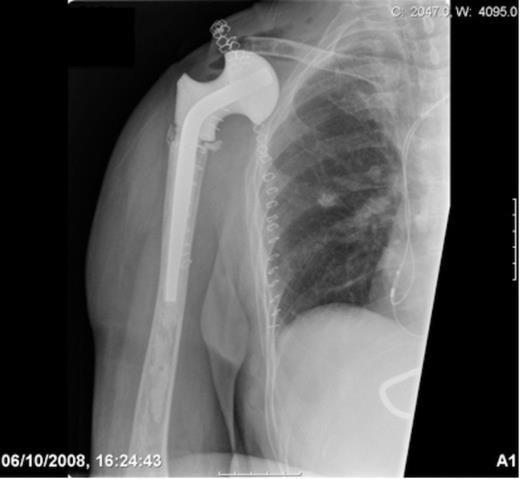

During the pre-operative consent process the patient stated if it was found that limb salvage was not technically possible intra-operatively, she did not wish to have a forequater amputation conducted and would rather the tumour be left untreated due to cosmetic concerns. A Tickhoff-Linberg procedure of the right shoulder was subsequently conducted with en-bloc resection of the scapula, distal clavicle and proximal humerus. In order to reconstruct the shoulder girdle, a hip spacer (spacer G by Orthodynamics) was cemented into the proximal humerus with the soft tissues tensioned appropriately. A synthetic mesh (LARS ligament by Corin) was then sutured over the prosthesis and secured to the osteotomised clavicular remnant and chest wall with non-absorbable sutures.

Post-operative radiograph demonstrating reconstruction using a hip spacer following extra-articular scapula resection